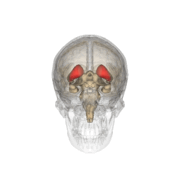

Caudate nucleus within the skull

Together with the putamen, the caudate forms the dorsal striatum, which is considered a single functional structure; anatomically, it is separated by a large white matter tract, the internal capsule, so it is sometimes also referred to as two structures: the medial dorsal striatum (the caudate) and the lateral dorsal striatum (the putamen). In this vein, the two are functionally distinct not as a result of structural differences, but merely due to the topographical distribution of function.

The caudate nuclei are located near the center of the brain, sitting astride the thalamus. There is a caudate nucleus within each hemisphere of the brain. Individually, they resemble a C-shape structure with a wider "head" (caput in Latin) at the front, tapering to a "body" (corpus) and a "tail" (cauda). Sometimes a part of the caudate nucleus is referred to as the "knee" (genu).[5]